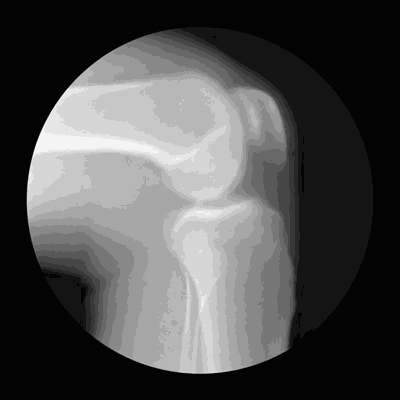

膝关节是人体最大、最复杂的关节,它仅仅靠一个狭小的接触面支撑着我们整个身体的重量。